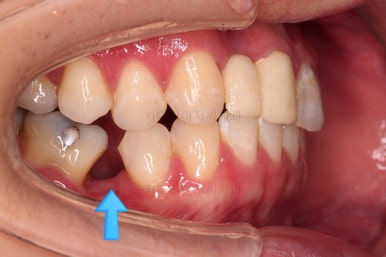

다행히 매복되었던 영구치는 잘 이동하였고요.

임플란트 자리도 적당한 크기로 점점 넓혀갑니다.

매복 영구치도 거의 다 배열되어 가고요.

임플란트 공간도 많이 확보되었습니다.

임플란트를 위한 기본 셋팅이 거의 완료되었습니다.

이 모습까지 13개월 걸렸네요.

굉장히 급한 마음으로 달려왔습니다.

지금부터는 임플란트, 보철 등을 진행하며 연산동치아교정은 보조적으로 진행하게 됩니다.